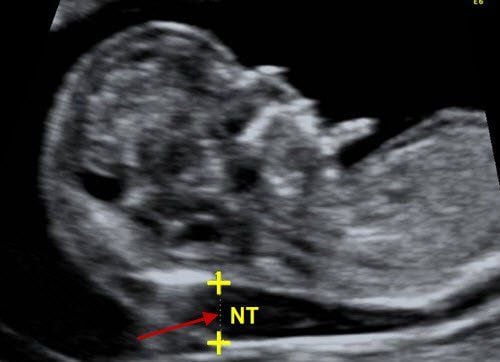

Is a nuchal translucency measurement of 1.2mm after 12 weeks of pregnancy a concern?

I am 15 weeks pregnant and had a nuchal translucency measurement of 1.2mm at 12 weeks and 5 days. I would like to ask the doctor if a nuchal translucency of 1.2mm after 12 weeks is concerning. I forgot to ask the doctor what the results for Trisomy 21 and Trisomy 18 mean.